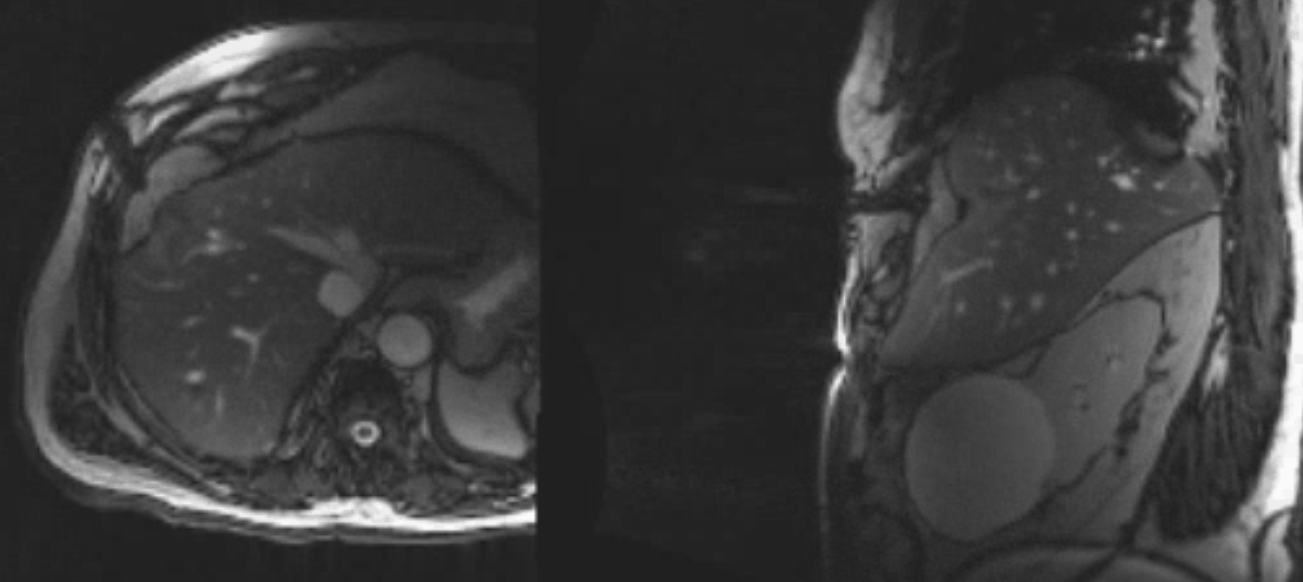

A small hepatocellular carcinoma is shown on MRI. It demonstrates arterial enhancement after gadolinium injection.

The same lesion is visible on non-contrast MRI (Trufi), ensuring easy targeting with MRI guidance.

Real-time MRI guidance is used to place the first cryoprobe into the lesion.

The ice ball is well visualised on all MRI sequences, ensuring complete coverage of the tumour with margins to spare.